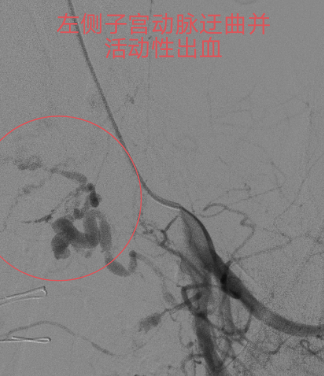

本着“生命至上”的原则,吴主任立即启动介入导管室为产妇施行“造影术”检查,造影发现产妇子宫动脉远端均有活动性出血,尤以左侧子宫动脉出血明显,血液不断外渗,病情紧急,止血治疗迫在眉睫!要知道产后大出血是非常凶险的疾病,不能有效止血可能需要切除子宫保命的!但患者才不到三十岁呀,正值青春年华,切除子宫对患者以后可是有非常大的影响。此时,能及时止血救命,又能保住子宫的微创介入止血法的优势就出来了!在患者及其家属的期盼和高度信任下,吴主任顺利为患者施行微创介入止血手术,术后患者子宫动脉出血停止,阴道出血减少,术后无需继续输血血压、血红蛋白均能维持稳定。术后经常规产后康复护理治疗后,患者病情稳定,没有异常阴道出血,现已康复出院。

血管造影见

双侧子宫动脉出血